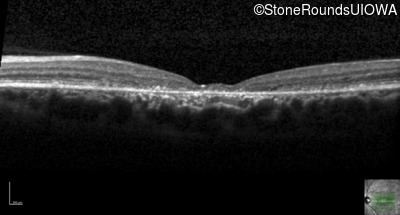

All three of the cardinal ophthalmic features of Mendelian macular dystrophies are present in this patient. The most striking features of the fundus exam are the numerous yellow flecks at the level of the RPE. Flecks are most commonly seen in AR Stargardt disease and pattern dystrophy although they may be seen in some of the rarer Mendelian maculopathies as well. The visual acuity in patients with AR Stargardt disease is often "worse than the fundus looks" while the acuity in pattern dystrophy is often quite good despite extensive flecks. The pedigree of this patient is compatible with ABCA4-associated Stargardt disease and the better than expected acuity is attributable to foveal sparing (see below). The onset of reduced acuity at age 10 is much more characteristic of ABCA4 disease than pattern dystrophy. Another feature present in this patient that is very frequently seen in Stargardt disease is peripapillary sparing. However, this sign can be seen in pattern dystrophy as well. When central atrophy is present in ABCA4-associated Stargardt disease it often somewhat shiny (which is uncommon with the geographic atrophy of pattern dystrophy or age-related macular degeneration). Some patients with ABCA4-associated Stargardt disease can have some preservation of the fovea giving a zonal "bullseye" appearance to the center of the macula. Sometimes this preservation is associated with preserved acuity as in this case. The outer nuclear layer (ONL) is much thinner than normal on OCT, indicative of photoreceptor loss. This is associated with a thinning of the ellipsoid zone which is usually many times brighter and thicker than the external limiting membrane (ELM). These two lines are essentially equal in intensity in this patient. The foveal sparing is seen on OCT only as a small bit of retinal convexity in the center of the atrophy coupled with a small bit of residual RPE flanked by bare Bruch's membrane. The presence of a robust I2e isopter on Goldmann perimetry places this patient in the least severe half of all Stargardt patients (see Schindler, et al., 2010). Most patients with ABCA4-associated disease are somewhat myopic as is this patient. Stargardt patients also tend to perform very poorly on pseudoisochromatic plates, even when their acuity is still fairly good as it is here.